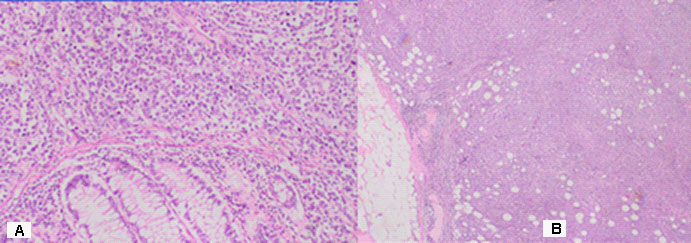

Part of a thick intestine with a size of 30 cm with a omentum. In the middle part of the resectеd colon, there is a tumor formation with a diameter of 10 cm. Eccentrically encompassing the intestine along the 10 cm. The tumor has a whitish color and macroscopically resembles fish meat. Seven lymph nodes were removed. Microscopic -Part of a thick intestine with a tumor histologically represented by diffuse cultivated tumor cells with scarce cytoplasm, circular polymorphic nuclei with visible nucleoli and high mitotic activity / over 10 mitoses per 10 high-power fields. The wall of colon with massive, diffuseinfiltration from large and medium-sized neoplastic cells. They have a slightly pronounced polymorphism, a dischositive way of growth, some of them with vesicular nuclei and prominent nucleoli (Figure 3A,C). Well taken out Reed-Sternberg like cells (Figure 3B). There are extensive zones with epithelium atrophy. The tumor infiltrates mucose, submucosa, smooth muscle layer, subset fat and serosis (Figure 4A). Morphology is a characteristic of MALT lymphoma. In three of the surveyed seven lymph nodes, a diffuse deletion structure was established due to tumor infiltration (Figure 4B). The resection lines are clean, without tumor infiltration. To establish the type of lymphoma, Immunohistochemical (IHC) analysis is imposed.

Figure 4: (A) The wall of colon with massive, diffuse infiltration from large and medium-sized neoplastic cells with slightly pronounced polymorphism, a dischositive way of growth, some of them with vesicular nuclei and prominent nucleoli H&E, x100. (B) In three of the surveyed seven lymph nodes, a diffuse deletion structure was established due to tumor infiltration H&E, x20.

DLBCL is neoplasm of large B lymphoid cells with nuclei at least 2× size of lymphocyte [20]. The pathomorphological characteristic is expressed by diffuse growth pattern with large cells (usually 5× normal lymphocytes) resembling immunoblasts (amphophilic cytoplasm, eccentric nuclei with one central nucleoli) or centroblasts (pale or basophilic cytoplasm, vesicular chromatin due to chromatin margination, 2 - 3 nucleoli, often near membrane), or rarely, anaplastic, associated with neutrophils [21]. In Figure 3 we present diffuse tumor cells with scarce cytoplasm, circular polymorphic nuclei with visible nucleoli and high mitotic activity / over 10 mitoses per 10 high-power fields. In Figure 4A is clearly seen the wall of colon with massive, diffuse infiltration from large and medium-sized neoplastic cells with slightly pronounced polymorphism, a dischositive way of growth, some of them with vesicular nuclei and prominent nucleoli. In three of the surveyed seven lymph nodes, a diffuse deletion structure was established due to tumor infiltration (Figure 4B).